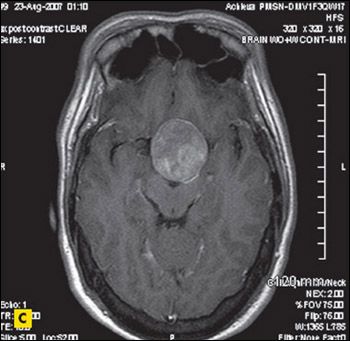

MRI scans of the brain revealed a 6 × 6 × 4-cm sellar mass with suprasellar and parasellar extension encasing the right cavernous sinus and carotid artery (Figure 2), which explained the vision loss.

Figure 2 – Sagittal (

A

), coronal (

B

), and axial (

C

) postcontrast MRI scans of the brain revealed a sellar mass of 6 × 6 × 4 cm with suprasellar and parasellar extension encasing the right cavernous sinus and carotid artery.